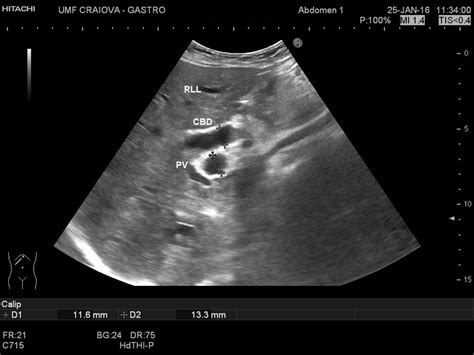

• Imaging Tests: Imaging studies such as ultrasound, computed tomography (CT) scan, and magnetic resonance cholangiopancreatography (MRCP) can visualize the bile ducts and detect dilatation.

Imaging tests are particularly important in diagnosing intrahepatic biliary ductal dilatation, as they provide detailed visual information about the bile ducts.

• intrahepatic biliary ductal dilation ultrasound